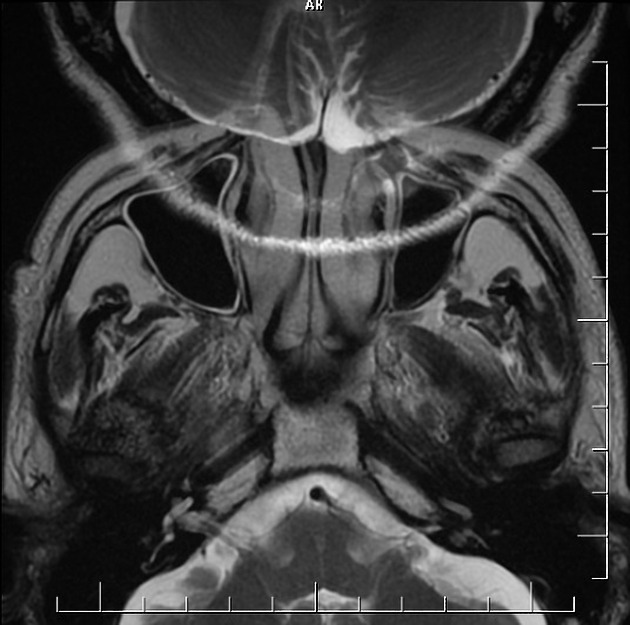

Different types of artifacts in brain MRI (a) Chemical Shift (b What Are Mri Artifacts This online presentation reviews the artifacts that are commonly encountered at mri. Mri artifacts are numerous and give an insight into the physics behind each sequence. They can be divided up into four major categories: Mri requires seamless integration and interplay of magnet, gradient coil system, rf system, and pulse sequence computer, each of. For each artifact, there is a. What Are Mri Artifacts.